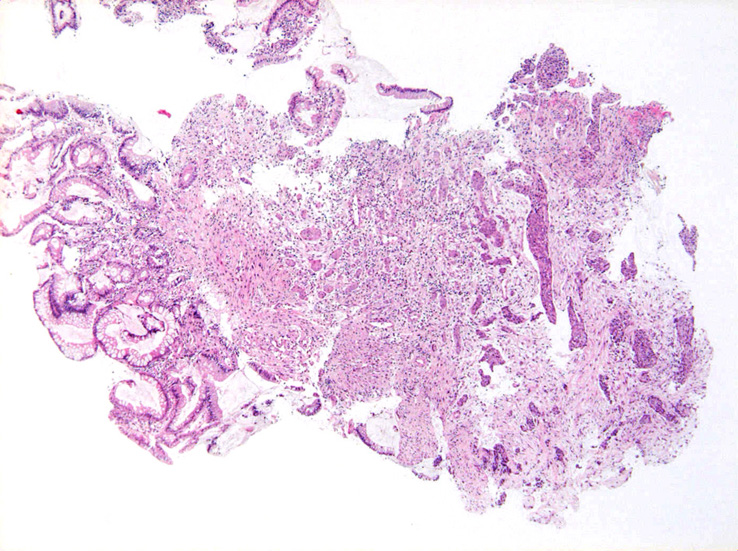

内視鏡所見:直腸は壁外圧排, S状結腸には壁外からの浸潤と思われる腫瘤があり狭窄している。この部位より生検

S状結腸粘膜生検組織所見:

粘膜筋板直下に小型胞巣を作って浸潤し炎症性の間質をともなう。 浸潤性増殖のわりに細胞は均一, そんなに異型性も強くない。apoptosisに陥った細胞が散在する。部位によっては胞巣状増殖細胞は細胞間橋がありそうな扁平上皮様に見える。深いところは線維性間質が増えてきて細胞は索状となりcarcinoidなども鑑別候補となるかもしれない。明らかな腺管形成, 粘液産生はみられない。35歳男性, わりとおとなしい扁平上皮癌様の組織か?と生検初見時に考えられた。desmoplasticな間質にもよく観察するとバラけた細胞異型が認められる。 (腫瘍胞巣①, ③)